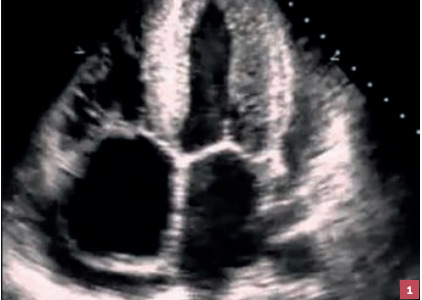

Le substrat physiopathologique est l’augmentation de la masse ventriculaire gauche, conduisant à une hypertrophie ventriculaire gauche (HVG ;fig. 1 ), souvent concentrique. Ainsi, le muscle cardiaque est épaissi et rigidifié. La relaxation et le remplissage myocardique sont perturbés. La dyspnée peut donc être liée soit au trouble de la relaxation par hausse des pressions de remplissage du VG et retentissement hémodynamique d’amont avec augmentation de la pression capillaire pulmonaire, soit à une coronaropathie secondaire à l’HVG par défaut de vascularisation.

L’HVG touche environ 20 % des hyper- tendus et augmente significativement le risque de maladie coronaire et d’insuffisance cardiaque. Pour la détecter, l’ECG, par la mesure de l’indice de Sokolow ou de Cornell, a une mauvaise sensibilité mais une bonne spécificité. Le déplacement de l’axe électrique du cœur vers la gauche ou l’apparition d’un bloc de branche gauche sur les ECG successifs est un signe évocateur utile en pratique courante.

Les échocardiographies transthoraciques (ETT) de contrôle, réalisées tous les 3 à 5 ans (en dehors de tout événement cardiovasculaire), sont importantes pour dépister cette atteinte d’organe cible témoignant du contrôle insuffisant de l’HTA.